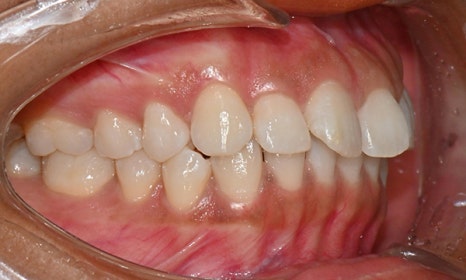

위아래 앞니 사이가 벌어져서 공간이 있었고, 앞니에 약간씩 배열이 틀어진 덧니가 있었습니다. 정면에서 보았을 때 윗니와 아래 앞니가 깊게 물려서 아래 앞니가 잘 보이지 않는 과개교합 양상을 보이고 있었습니다. 또한 왼쪽 아래 작은 어금니가 90도 앞으로 돌아가서 좌측 치아 배열 및 교합이 좋지 않은 상태였습니다.

초진시 구내사진 (2025. 3.31)

교정 마무리 후 사진으로 위아래 치아 배열이 개선되었고 공간이 모두 닫혔습니다. 위아래 앞니가 깊게 물리는 과개교합도 처음에 비하여 많이 개선되었습니다. 다만 아래 작은 어금니 배열로 인하여 왼쪽 어금니 교합은 아직 완벽하지 않은 상태로, 추후 본국으로 돌아가서 자료를 transfer 해드려서 이어서 치료를 받기로 하셨습니다.